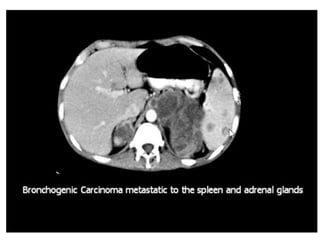

This document discusses the spleen and causes of splenomegaly (enlarged spleen). It begins by thanking radiologists for their assistance. Simple cyst criteria are outlined. Splenogonadal fusion and sarcoidosis are mentioned. The main causes of splenomegaly are then listed, including infections, portal hypertension, hemolytic anemias, hematological malignancies, infiltrative disorders, collagen vascular disorders, and congestive cardiac failure.